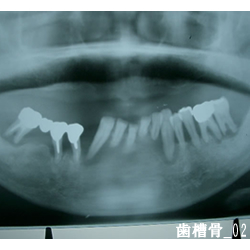

- レントゲンでの状態

- レントゲンで調べると、周囲の骨が溶けており、放置しておくと、どんどん骨の吸収が進みます。